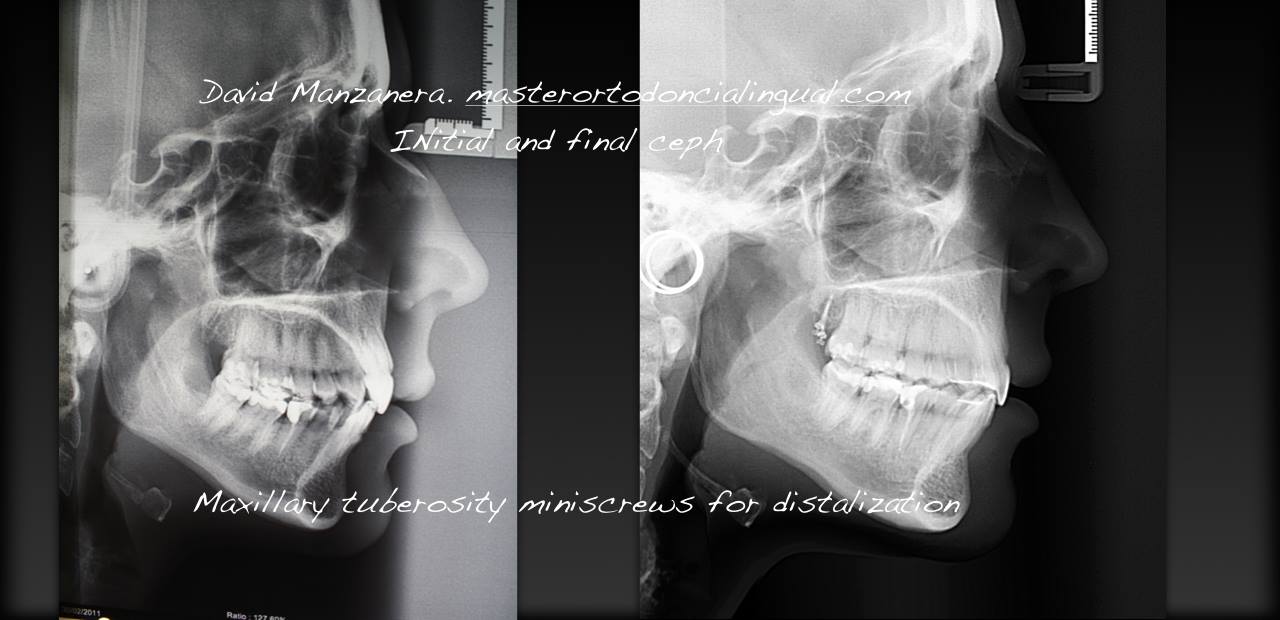

La paciente que os enseño tenía falta de espacio superior e inferior, hicimos la extracción de las muelas del juicio superiores e inferiores y se colocaron minitornillos para ganar espacio hacia atrás. Llevó ortodoncia invisible lingual con sistema incognito durante un año y medio en nuestra clínica de Valencia.

Podeís ver las fotos de antes y después, una vez retirada la ortodoncia lingual y los minitornillos, que se retiran sin necesidad de anestesia y sin dolor alguno.

ToggleAntes y después tratamiento ortodoncia inicial con microtornillos